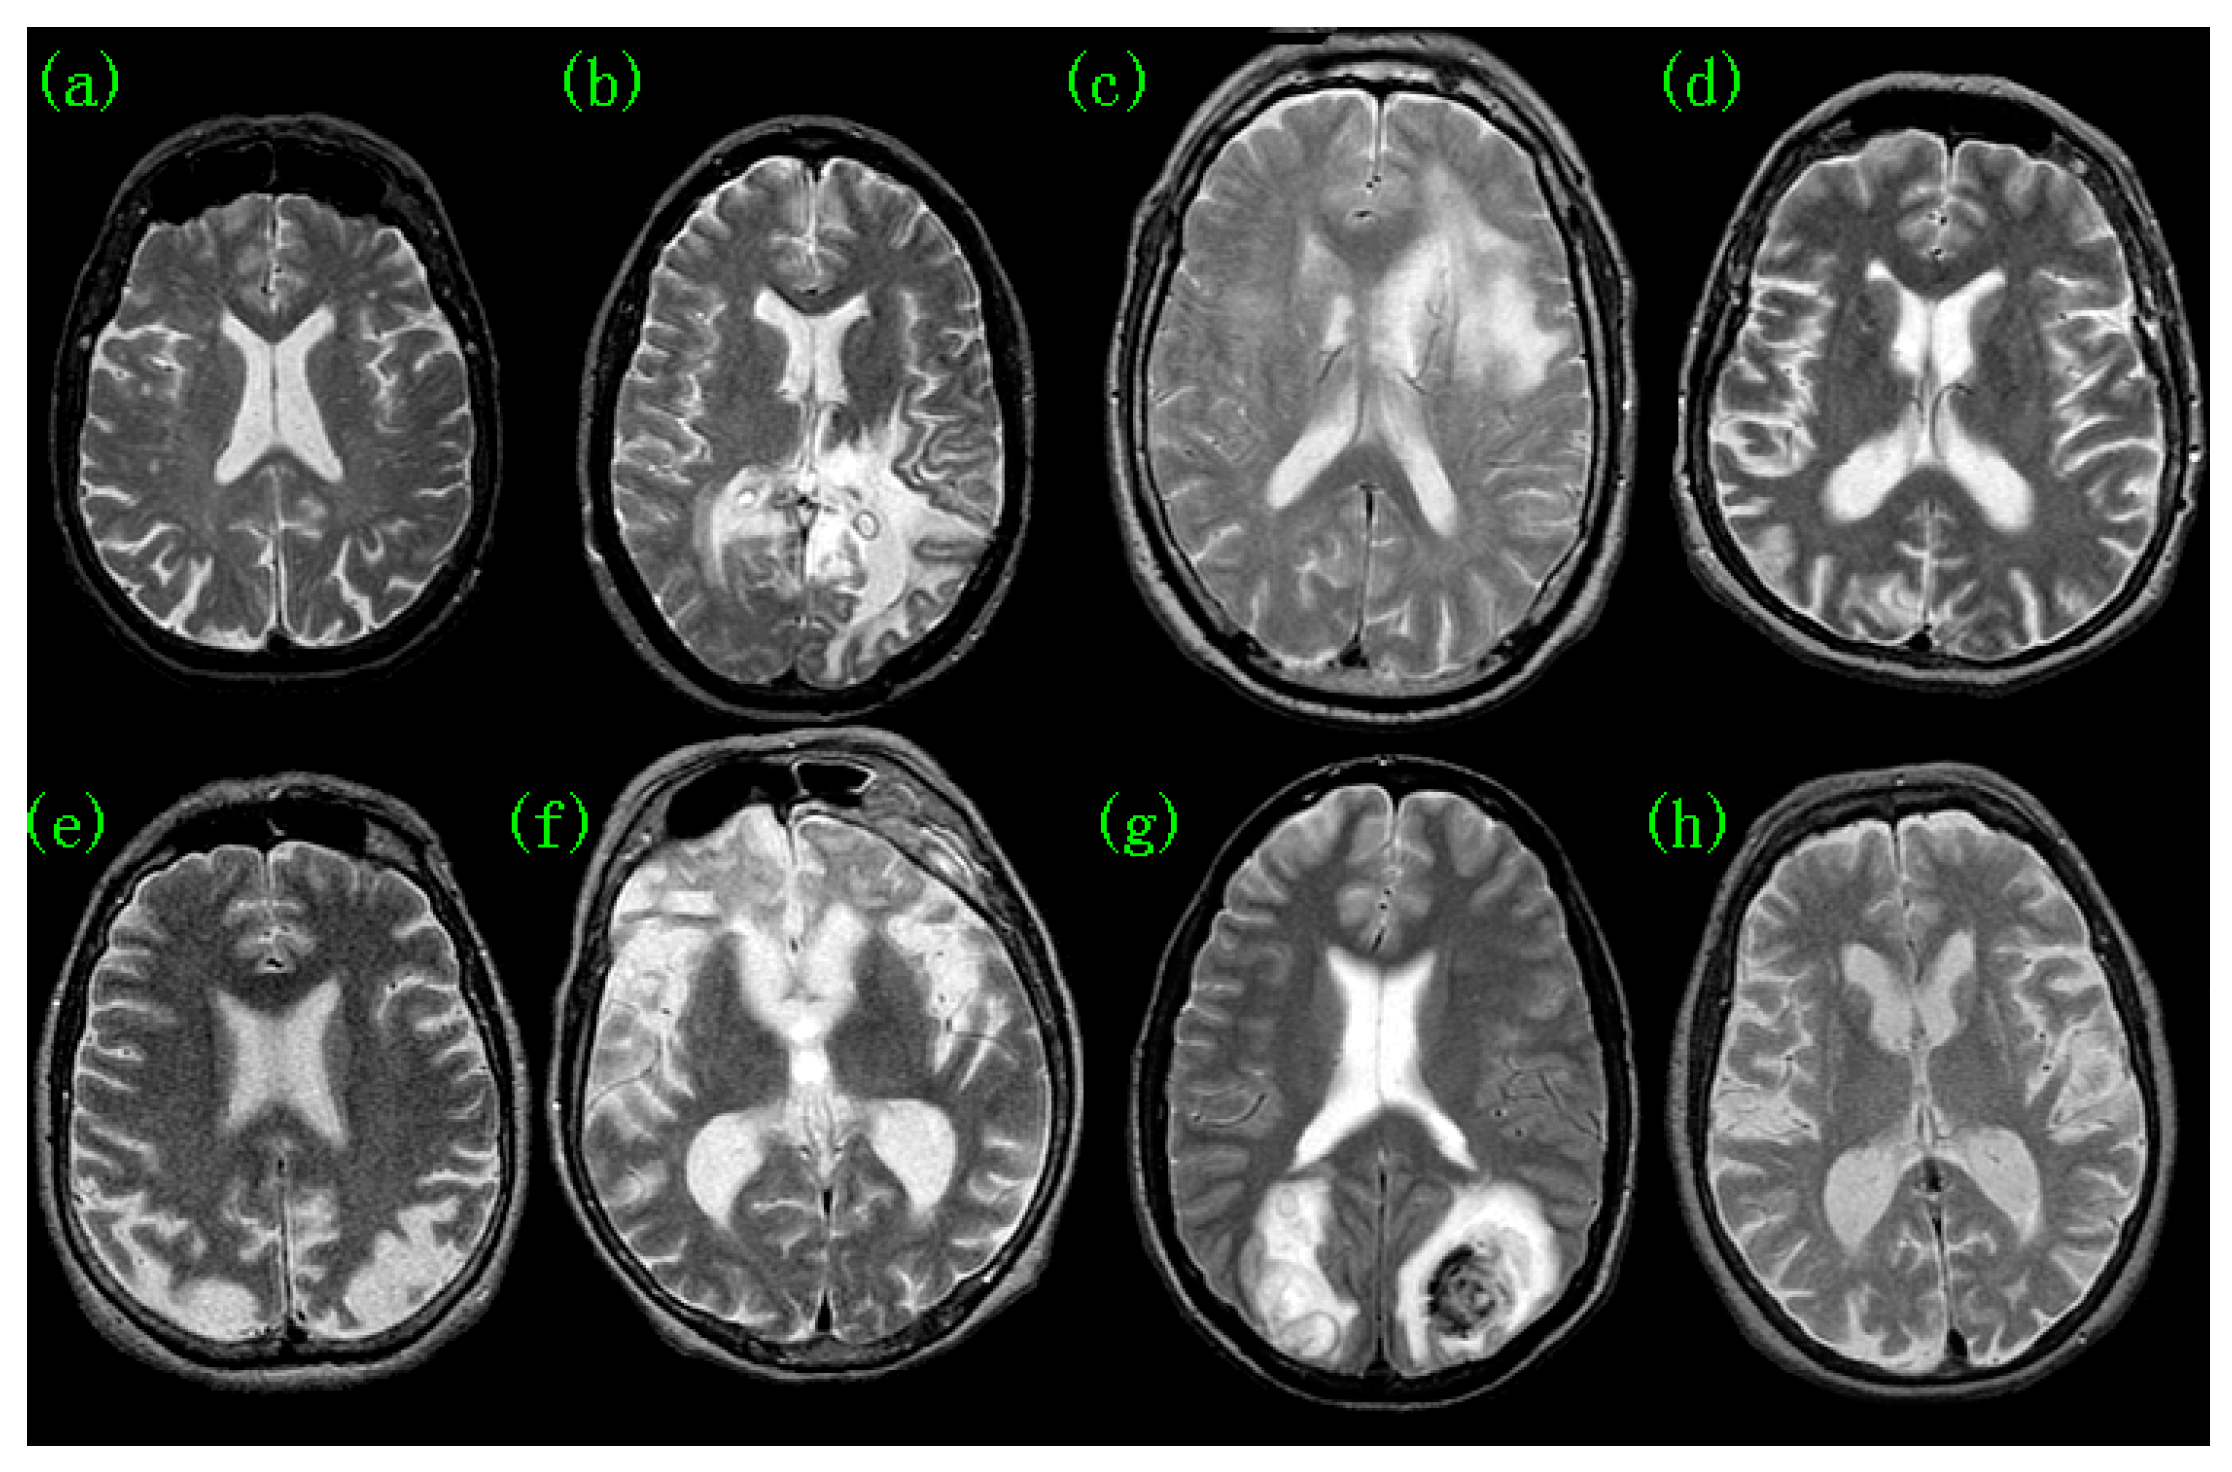

2. Pathological Brain Detection

- Zhang, Y.-D.; Wang, S.-H.; Yang, X.-J.; Dong, Z.-C.; Liu, G.; Phillips, P.; Yuan, T.-F. Pathological brain detection in MRI scanning by wavelet packet Tsallis entropy and fuzzy support vector machine. SpringerPlus 2015, 4, 1–16. [Google Scholar] [CrossRef]

- Zhang, Y.; Yang, J.; Wang, S.; Dong, Z.; Phillips, P. Pathological brain detection in MRI scanning via Hu moment invariants and machine learning. J. Exp. Theor. Artif. Intell. 2016, 29, 299–312. [Google Scholar] [CrossRef]